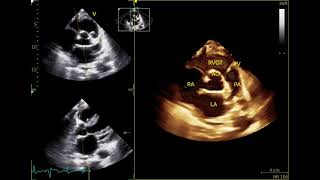

Welcome to EchoDx Hub, your dedicated space for mastering echocardiography through real clinical cases. We specialize in showcasing abnormal echo images and videos, helping you recognize key patterns, understand pathology, and sharpen your diagnostic skills.

To build a high-quality educational archive of diverse echocardiographic abnormalities and cardiovascular diagnostics—for students, sonographers, and healthcare professionals passionate about cardiac imaging.

Valvular, myocardial, pericardial, and congenital abnormalities